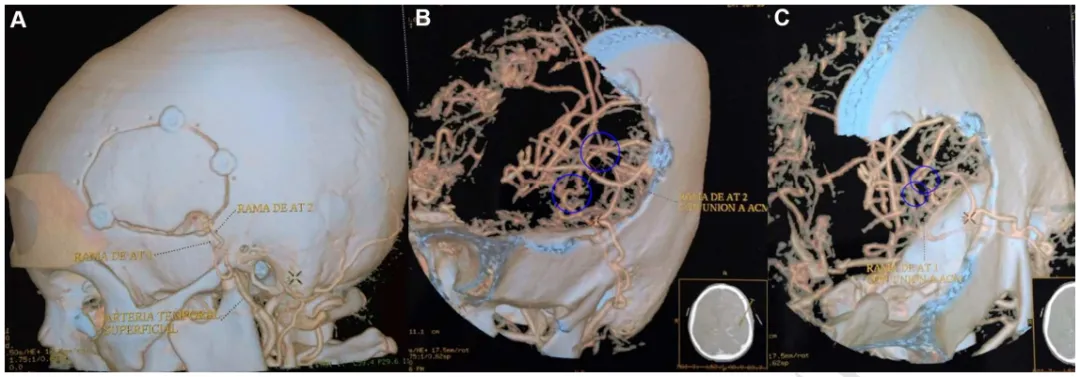

图2:浩一术后CTA的3D重建显示开颅手术大小,以及在左侧颞浅动脉和左侧大脑中动脉之间进行的两次搭桥血管重建。